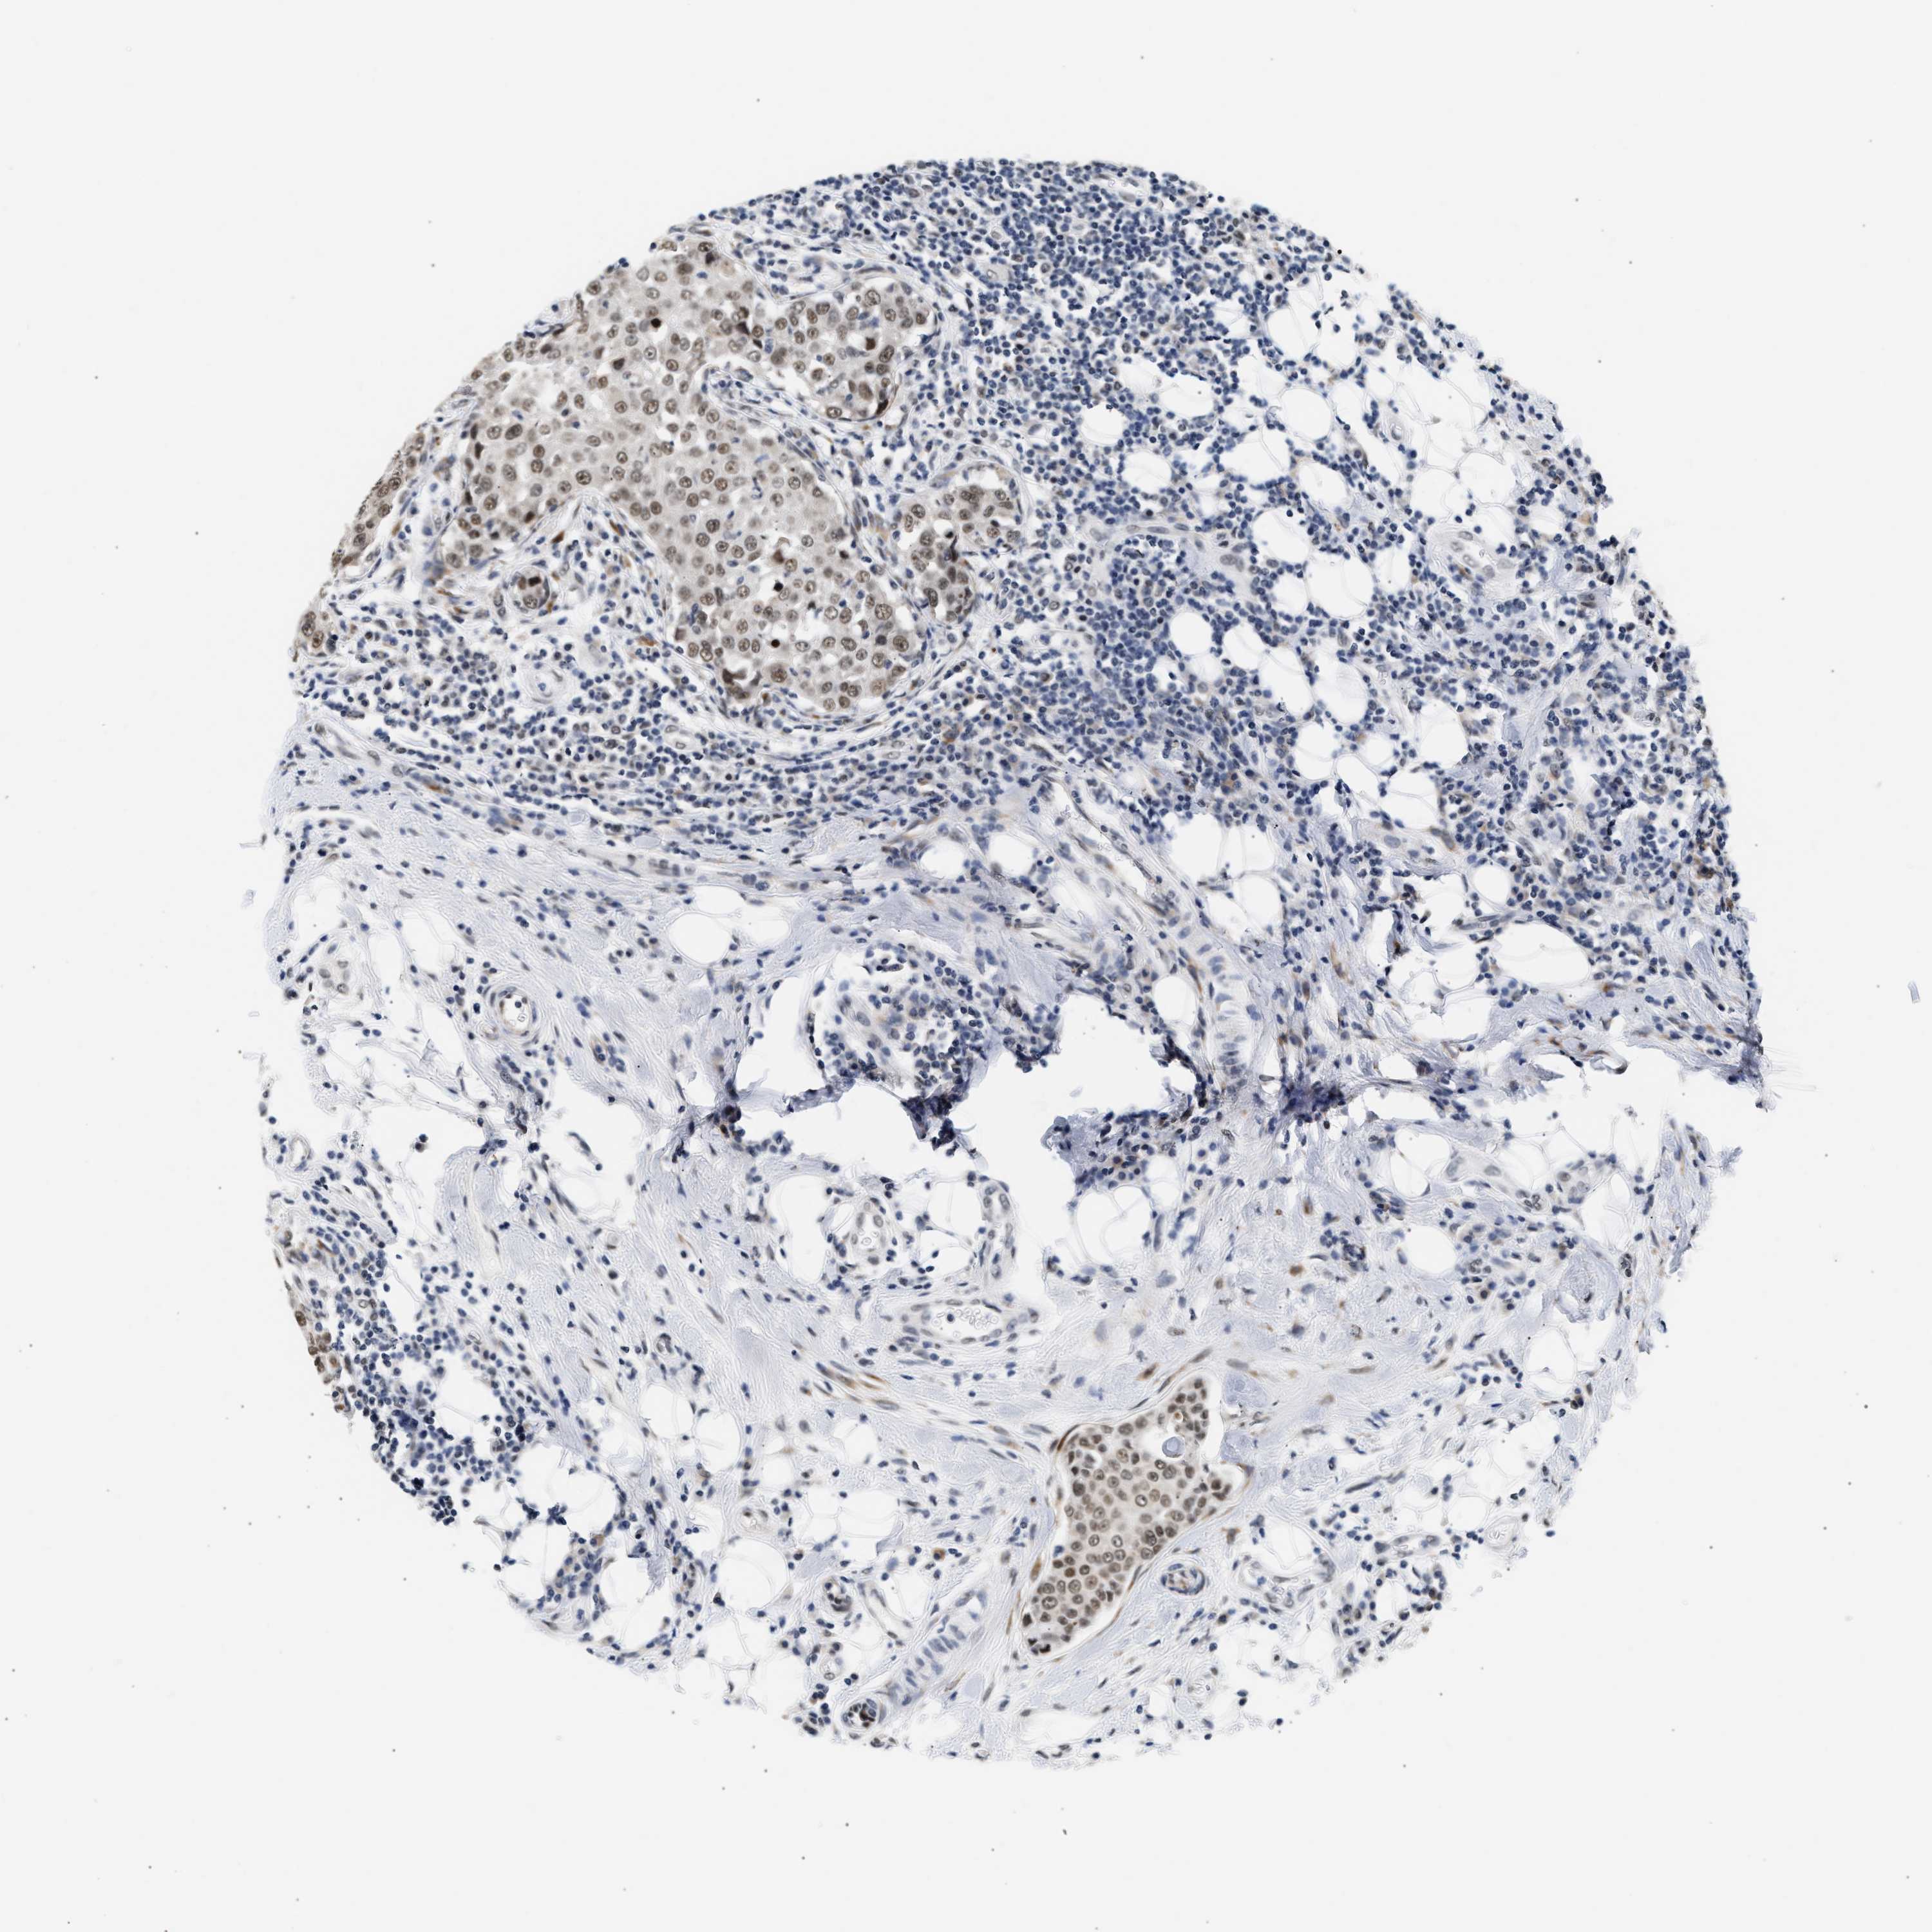

CANCER BREAST CANCER Show tissue menu

BRCA TCGA BRCA VALIDATION PROTEIN EXPRESSION